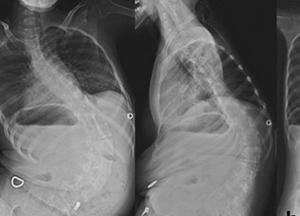

СМА второго типа характеризуется развитием мышечных и скелетных деформаций, нарушением дыхания, отставанием в моторном развитии. Ребенок начинает ползать, пытается сесть, но со временем это становится невозможным.

Самой быстропрогрессирующей формой СМА является первый тип. Большинство детей не доживают до двухлетнего возраста из-за серьезных проблем с дыханием. Поэтому они нуждаются в своевременной респираторной поддержке. Кроме этих четырех типов СМА, существуют также переходные формы заболевания, которые дополняют традиционную классификацию.

Поддерживающая реабилитация пациентов со СМА включает выполнение специальных упражнений для тела, дыхательной гимнастики, ношение жестких корсетов (при сколиозе) и/ или шин, шейных бандажей, ортезов. Кроме того, очень важно следить за состоянием костей — систематически исследовать их минеральную плотность или выполнять сканирование. Также ребенку со СМА требуется специальное питание, откашливатель, аппарат неинвазивной или инвазивной вентиляции легких, кислородный концентратор, пульсоксиметр.